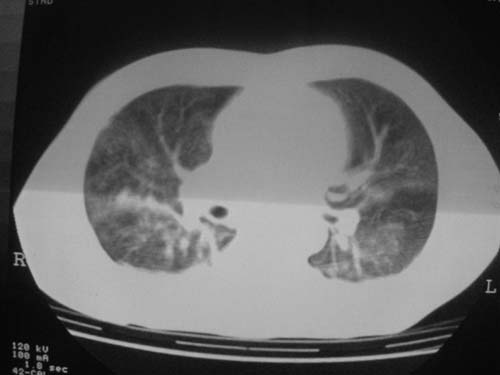

这是第五天拍的ct,纵隔窗我没都传,实在是太费时,请教各位老师,此病人有肺水肿吗?帮忙分析一下

患者第三天后逐渐加重,不符合肺挫伤表现,因为肺挫伤大部分是以外伤后24小时或36小时为发病高峰,之后就开始吸收。

不知道具体外伤的情况(部位,方式‘程度等),肺内病变范围较广,上下叶都有,似乎与肺挫伤不相符合,是应该看看临床治疗详情,特别是输液出入量,以前见过类似的病人,间质性肺水肿可能大!等待结果,盼盼盼!